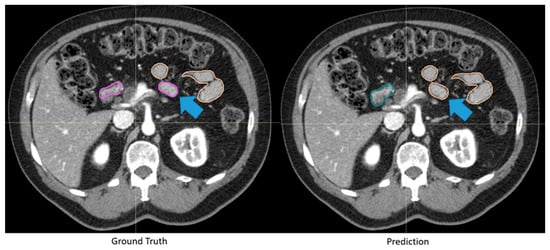

Figure 2.

Automatically generated duodenum and small bowel contours with low Dice similarity coefficient (0.61) but were deemed clinically acceptable. Although the automatically generated contour (green: duodenum, yellow: small bowel) deviated from the “ground truth” (pink: duodenum, yellow: small bowel), as highlighted by the blue arrows, the difference was deemed insignificant by clinicians because of the identical dose constraints between the two segmented organs.